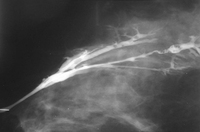

Ductogram demonstrating multiple intraductal papillomas

Courtesy of Dr Nancy Pile, University of Louisville; used with permission